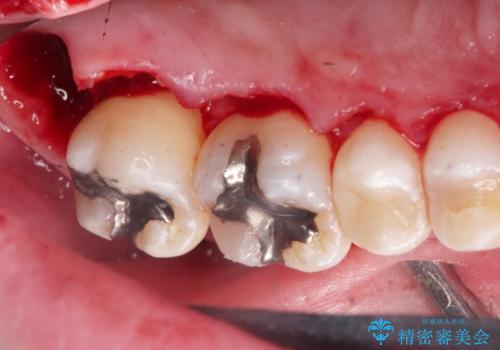

2. 縁下歯石のクリーニングの治療中

2.